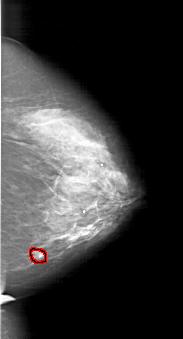

A_1218_1.RIGHT_CC

RIGHT_CC LINES 6091 PIXELS_PER_LINE 3286 BITS_PER_PIXEL 12 RESOLUTION 43.5 OVERLAY

FILE: A_1218_1.RIGHT_CC.OVERLAY

TOTAL_ABNORMALITIES 1

ABNORMALITY 1

LESION_TYPE MASS SHAPE LOBULATED MARGINS ILL_DEFINED

ASSESSMENT 4

SUBTLETY 2

PATHOLOGY MALIGNANT

TOTAL_OUTLINES 1

BOUNDARY